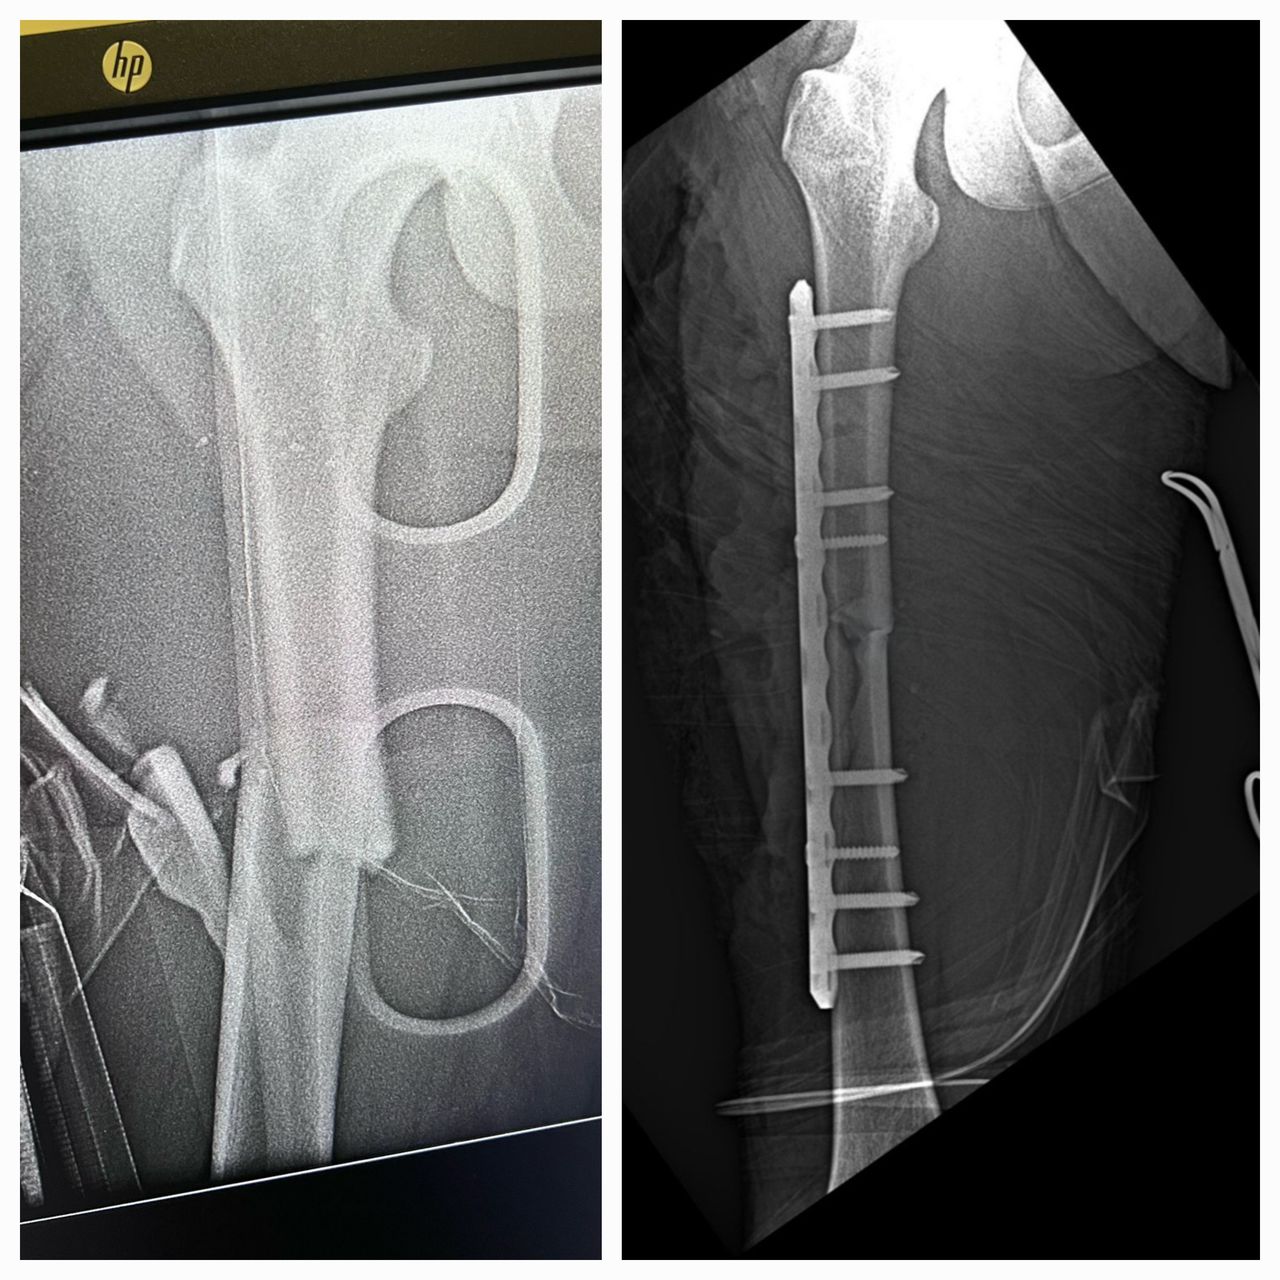

Fotos y videos